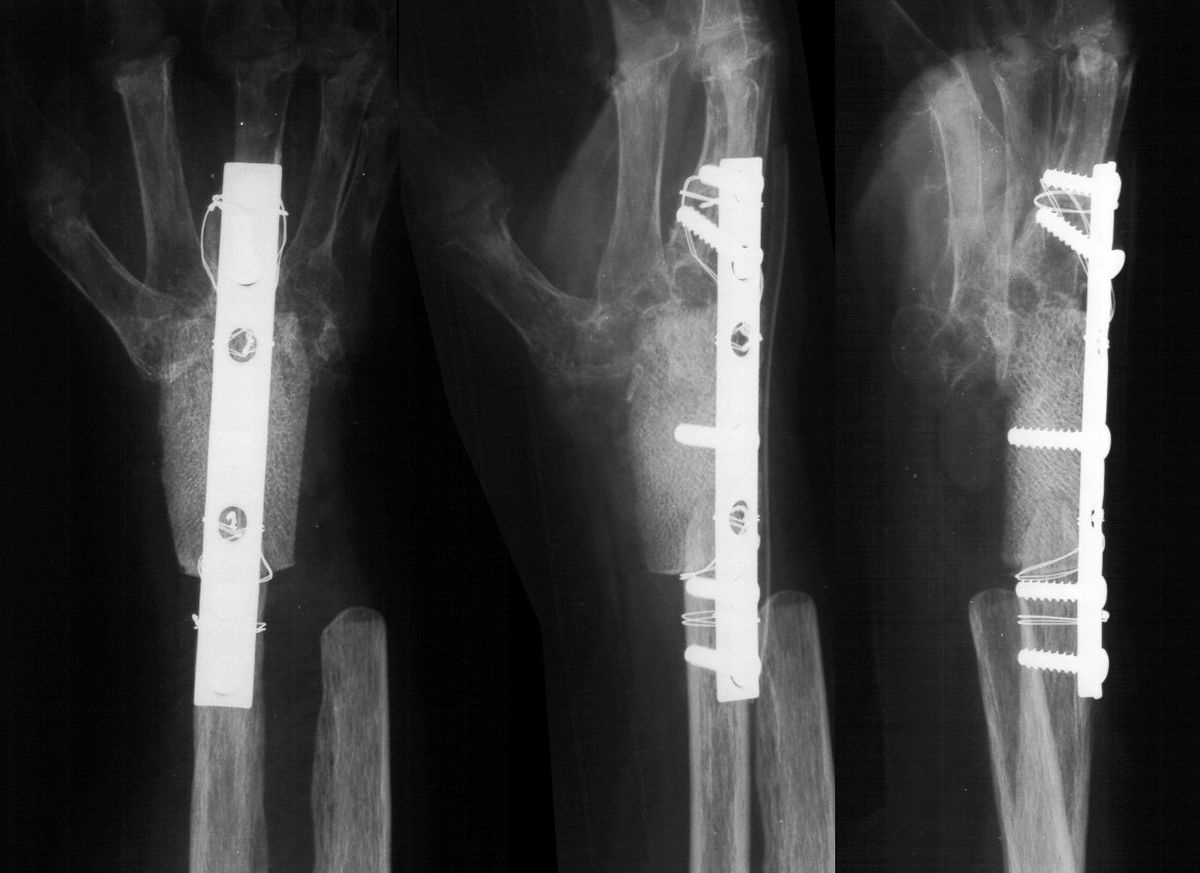

She was treated with wrist arthodesis, using a sculpted fresh frozen femoral head allograft and a cerclage reinforced plate and screw fixation.

Highslide